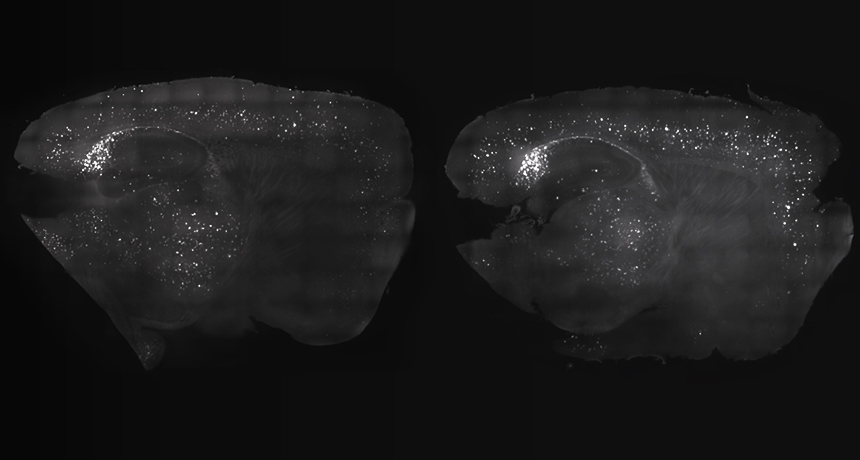

DISAPPERING ACT Precisely timed lights and sounds reduced amyloid-beta plaques in a mouse brain (left) compared with the brain of a mouse that didn’t receive the treatment (right).

When the mice were treated with both flickering lights and clicks, the effect was even stronger, Tsai says. The combined treatment led to fewer A-beta plaques across a big stretch of the brain, including the hippocampus and the prefrontal cortex, an area important for complex thinking. What’s more, the microglia seemed to swarm into a feeding frenzy. “Microglia pile up on each other, all congregated around the amyloid plaques,” Tsai says.